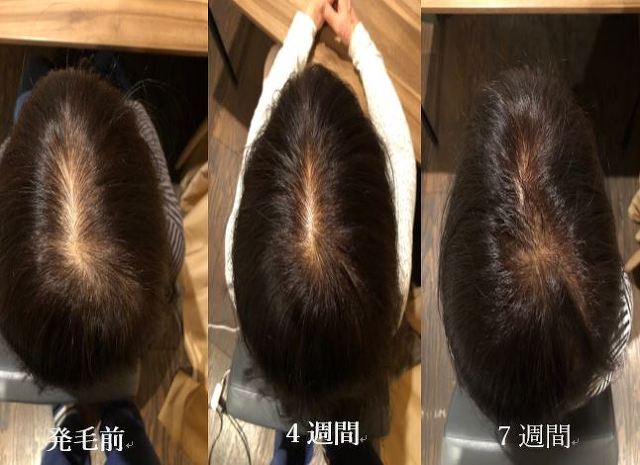

★発毛・薄毛部門からのお知らせ★

⚡薄毛・育毛にお困りの方に朗報です⚡

☑市販の育毛剤じゃ効果が出ない

☑抜け毛が気になってきた

☑全体的に髪のボリュームがなくなってきた

☑親族に薄毛の方がいる

こんな方はぜひご相談ください!

悩んでいる時間がもったいない!

確実に満足のいく結果を出します!

「受けてみたいけど…踏ん切りがつかない」という方もいらっしゃると思います。

嬉しいお知らせ!初回のカウンセリングは無料です。

完全予約制なので貸切でご相談いただけますので内容を聞かれる心配もなし!

それでもまだ迷ってる方は、もう少し迷われていて下さい。

あなたの決心がつくまで私は見捨てません。

あなたにとって「人生最後の発毛治療」にしましょう。

本気で私もあなたと向き合います!

「発毛のカウンセリングをお願い!」とご連絡下さい。